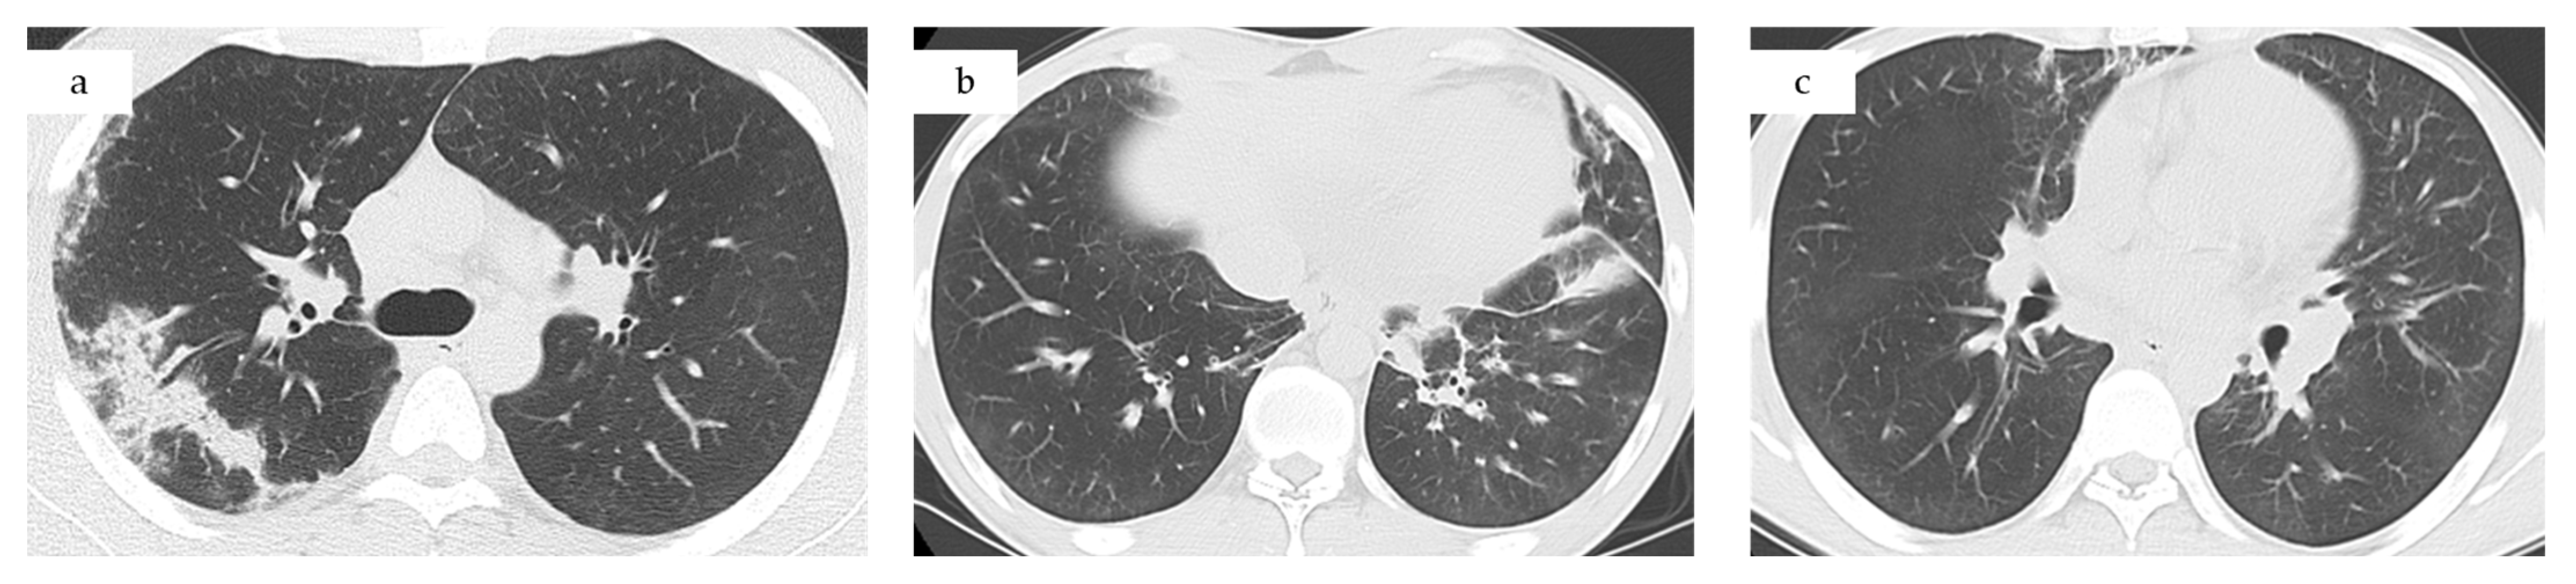

- Computed tomography (CT) chest/abdominal: recurrent bilateral ground-glass opacities and patchy consolidations without pleural effusion or lymphadenopathy, consistent with relapsed CEP. Abdominal and pelvic organs were unremarkable (Figure 1c).